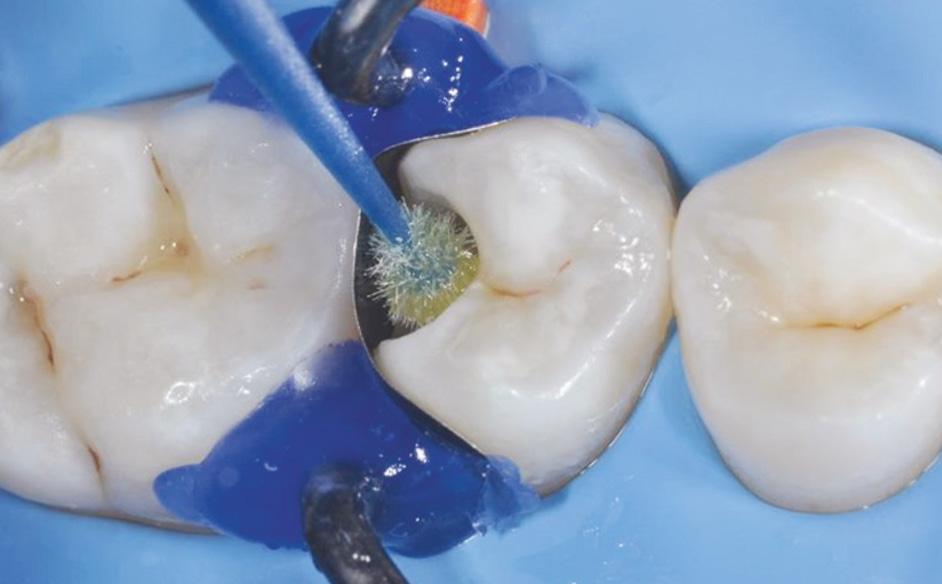

Fig. 5: Caries removal and cavity preparation. Caries detection dye was used as a Fig. 6: A 15 second selective enamel etch using 3M™ Scotchbond™ Universal Etchant followed by rinsing and air drying. Fig. 7: 3M™ Scotchbond™ Universal Adhesive was scrubbed into the preparation for 20 seconds followed by air-drying and light-curing with 3M™ Elipar™ LED Curing Light for 10 seconds.* Fig. 8: 3M™ Filtek™ One Bulk Fill Restorative A3 was placed in one increment. The composite was cured for 10 seconds on the occlusal surface.*